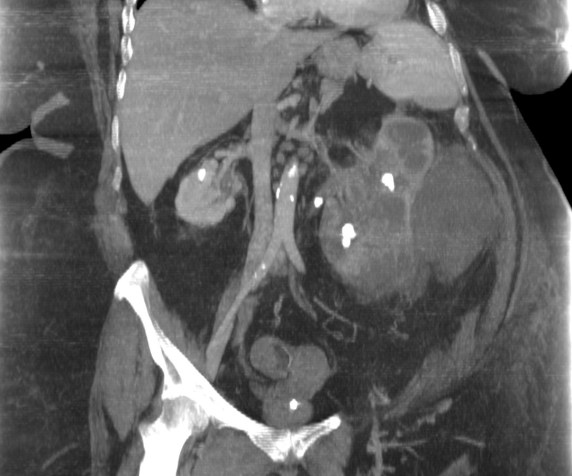

- Aumento difuso del tamaño y pérdida del contorno renal.

- Litiasis coraliforme: cálculo central en pelvis renal contraída (también puede existir calcificaciones intraparenquimatosas). La TC es la mejor técnica para identificar las litiasis.

- Riñón no funcionante (pobre o nula eliminación del medio de contraste en el riñón afectado).

- Cálices renales dilatados (áreas hipodensas) de apariencia multiloculada que se asemeja a una «pata de oso».

- También pueden darse abscesos o áreas de necrosis parenquimatosa.

- Cambios inflamatorios que excede los límites del riñón y genera colecciones periféricas o extensión hacia vísceras vecinas. Pueden darse abscesos en el psoas y fístulas (cutáneas o colónicas) que indican progresión de la enfermedad.

Paciente mujer de 62 años que acude por decaimiento general con fiebre y dolor en flanco izquierdo. Ingresa en UVI por signos de sepsis

Nos cuenta antecedentes de pielonefritis e hidronefrosis crónica.

Hallazgos en imagen:

Estos hallazgos pueden ser dificiles de interpretar, ya que una paciente con hidronefrosis crónica y litiasis en el uréter puede haber sufrido una obstrucción que origina un cuadro de dolor en FRI con ruptura de cálices y colección extra axial. Otra probabilidad puede ser un angiomiolipoma que ha roto un aneurisma y ha producido un sangrado. También podríamos estar ante una pionefrosis aunque dada dada la clínica, los antecedentes y al observar los hallazgos en TC podríamos establecer la sospecha de pielonefritis xantunogranulomatosa con alta probabilidad. La confrimación vendrá dada con la nefrostomía y estudio de anatomía patológica.